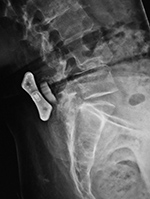

Harms vertebral cage (lateral view) |

| There is a vertebral cage and side plate and screws in the lower thoracic spine for treatment of a spinal tumor. From Hunter, 1994 |

| Vertebral corpectomy with vertebral cage and left lateral side plate |